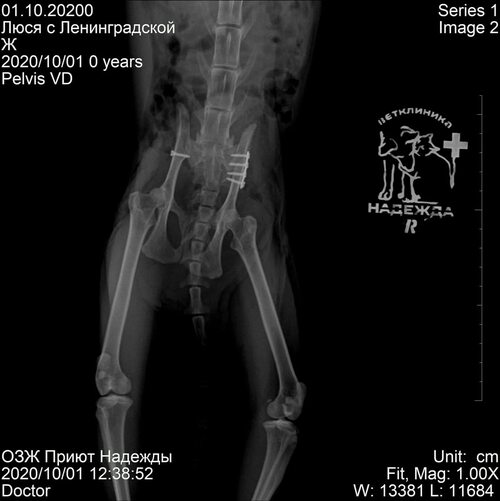

Подвывих тазобедренного сустава рентген

Вывих тазобедренного сустава рентген

Перелом таза и бедра у кошки